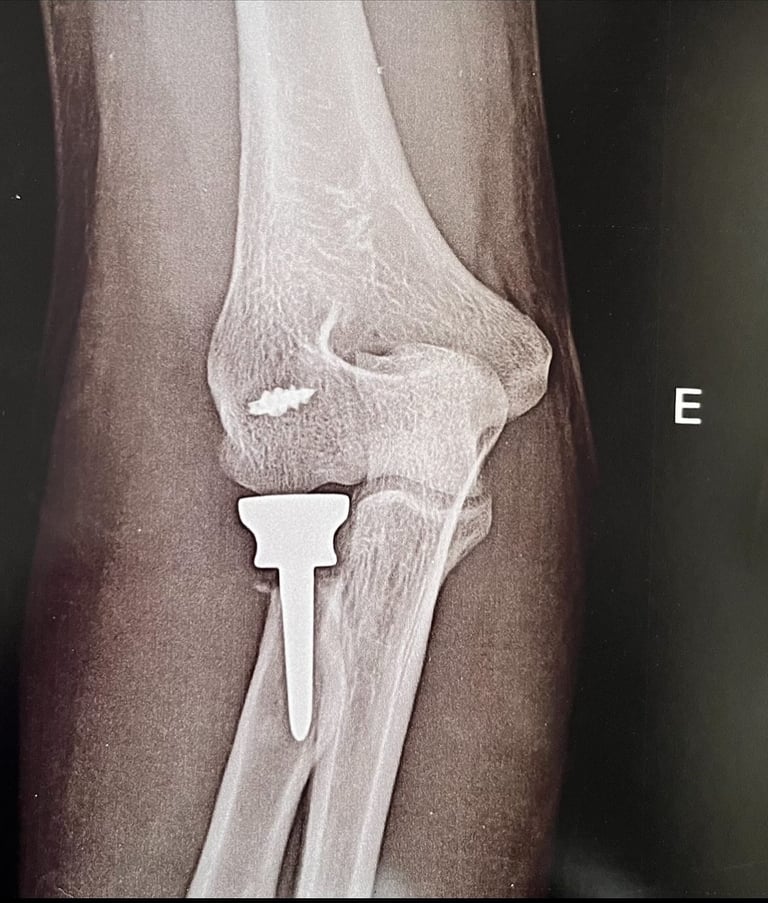

Patologias do Cotovelo

Tratamento de epicondilite lateral (cotovelo de tenista), lesões de tendões, instabilidades e outras afecções da articulação do cotovelo.